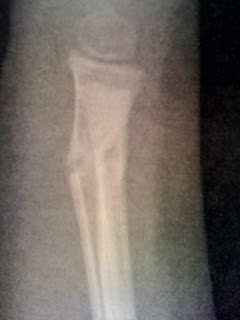

wearing her cast. The doctor says two more weeks in a splint and

light duty.

She broke it at grandma's after a fall while sledding during the first

snow this year.

I feel bad for her. We have all been so excited for her to get it

off. Doctor says she will be fine.... Once it heals.